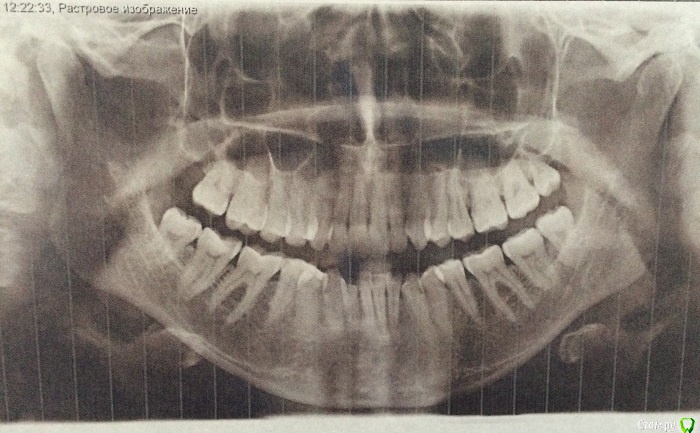

lalafa Опубликовано 16 августа, 2017 Поделиться Опубликовано 16 августа, 2017 (изменено) Здравствуйте, помогите, пожалуйста, советами.Мне 29 лет. Хронические заболевания - гранулезный фарингит, гастрит, ГЭРБ, сколиоз. У меня генерализованная рецессия десны, катаральный гингивит, пародонтальных карманов нет. Рекомендовано ортодонтическое лечение. НО ортодонты предупредили, что велика вероятность продолжения рецессии десны во время лечения и ухудшения ситуации. Посетила 2 пародонтологов, мнения противоположные. Один рекомендует операцию по закрытию рецессии методом пересадки трансплантата с неба. Хочет оперировать до ортодонт лечения самые проблемные зубы - клыки на нижней челюсти и 4ку. Мотив - утолщить десну, чтобы она выдержала брекеты и не рецессировала еще больше.Другой пародонтолог говорит, что так как именно эти зубы "не стоят в зубной дуге" (цитата врача) трансплантат с неба не приживется и результата не будет. Советует делать операцию после снятия брекетов на прямые зубы.Вопросы:1) Насколько в принципе опасно при такой рецессии проводить ортодонтическое лечение? зубы могут расшатываться и выпасть в процессе лечения?2) Закрывать рецессию до брекетов или после? Действительно, на таких вывернутых зубах не приживается трансплантат?3) Постоянно мучаюсь с катаральным гингивитом. Прохожу Проф чистку раз в 6 месяцев, но без толку. за чистотой слежу и самостоятельно, но скученные зубные ряды все равно провоцируют гингивит. Можно надеяться, что после брекетов гингивит вылечится? Изменено 16 августа, 2017 пользователем lalafa Ссылка на комментарий

lalafa Опубликовано 17 августа, 2017 Автор Поделиться Опубликовано 17 августа, 2017 Про гигиену чищу зубы как показал стоматолог, по схеме.Нитью больно пользоваться, потому что сильная скученность.После проф чистки гингивит все равно есть, просто десны не кровоточат, но они красные и припухшие. фото сделаны после недели применения ополаскивателя, от которого сильно желтеют зубы, поэтому такой вид, как будто проблемы с гигиеной.Скажите. пожалуйста, на снимке есть признаки пародонтоза? Ссылка на комментарий

Art 7 Опубликовано 17 августа, 2017 Поделиться Опубликовано 17 августа, 2017 ополоскиватель не окрашивает зубы, он окрашивает налёт. пластику до брекетов, вы не первая со скученностью, есть и сложнее ситуации когда пациенты справляются. породонтоза у вас нет Ссылка на комментарий